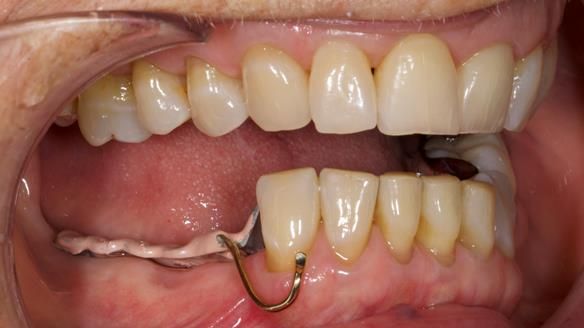

Welcome to Newsletter 61. In this edition, I walk through the process of creating and fitting a metal based lower partial denture for Joyce, a fit and healthy 76 -year-old woman.This issue shows the complete protocol workflow for achieving an exceptionally well-fitted and aesthetically good RPD.

Welcome to Newsletter 61. In this edition, I walk through the process of creating and fitting a metal based lower partial denture for Joyce, a fit and healthy 76 -year-old woman.

The missing lower right teeth to be replaced with a metal based partial denture.

The detailed clinical situation and treatment process are outlined below, with clinical work provided by me and technical work by Rowan Garstang. The treatment spanned six visits for denture fitting and one review.